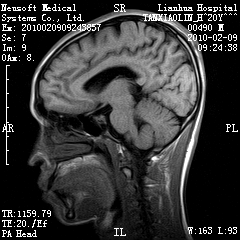

20岁男性患者,平时偶有头痛而无其他不适,现因持续头痛服药后无缓解而来院就诊。

松果体囊肿?

松果体区占位继发轻度脑积水?该患者有ct资料,我已发上。

考虑松果体囊肿。